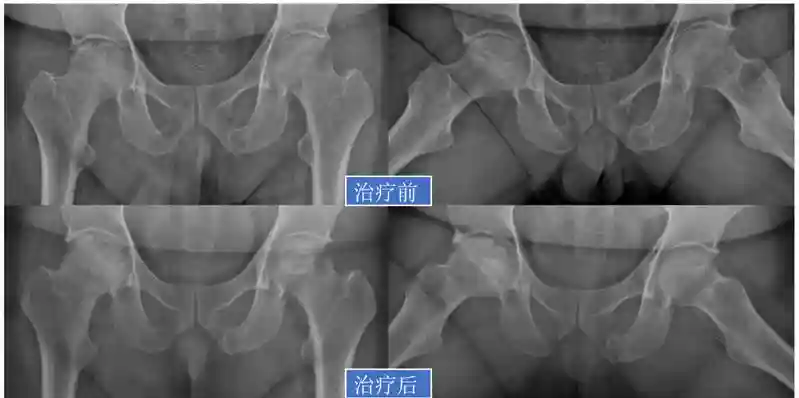

44岁的陈先生因为做生意经常要应酬喝酒,导致双侧股骨头坏死,他走进陈镇秋教授诊室时一瘸一拐非常辛苦。在来这里之前,他已经去过几家大医院,都建议他做手术或者等待关节置换。

陈镇秋教授为他进行仔细检查后,发现他的股骨头虽然坏死了,但外侧壁仍比较完整,属于保守治疗效果比较好的类型。详细沟通后患者也愿意积极配合,愿意戒酒并使用双拐保护。

接下来,他接受了中成药和康复治疗等保守治疗方法,3个多月后就不需要使用双拐了,3年后随访,他的股骨头修复良好,无塌陷,双髋无疼痛,功能良好。